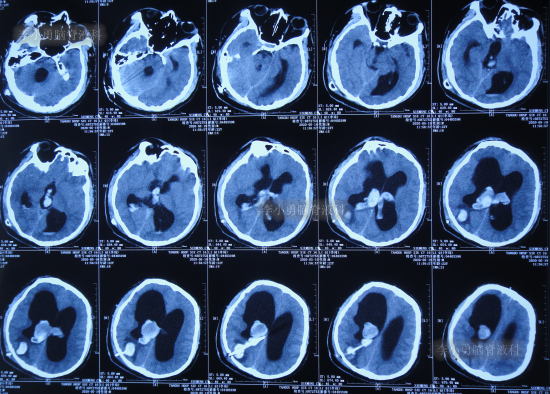

1个月后即2020年5月6日,为治疗脑积水,至陕西省西安市某三甲医院就诊,查头颅核磁示脑积水(图-4)。

图-4:2020年5月6日头颅核磁